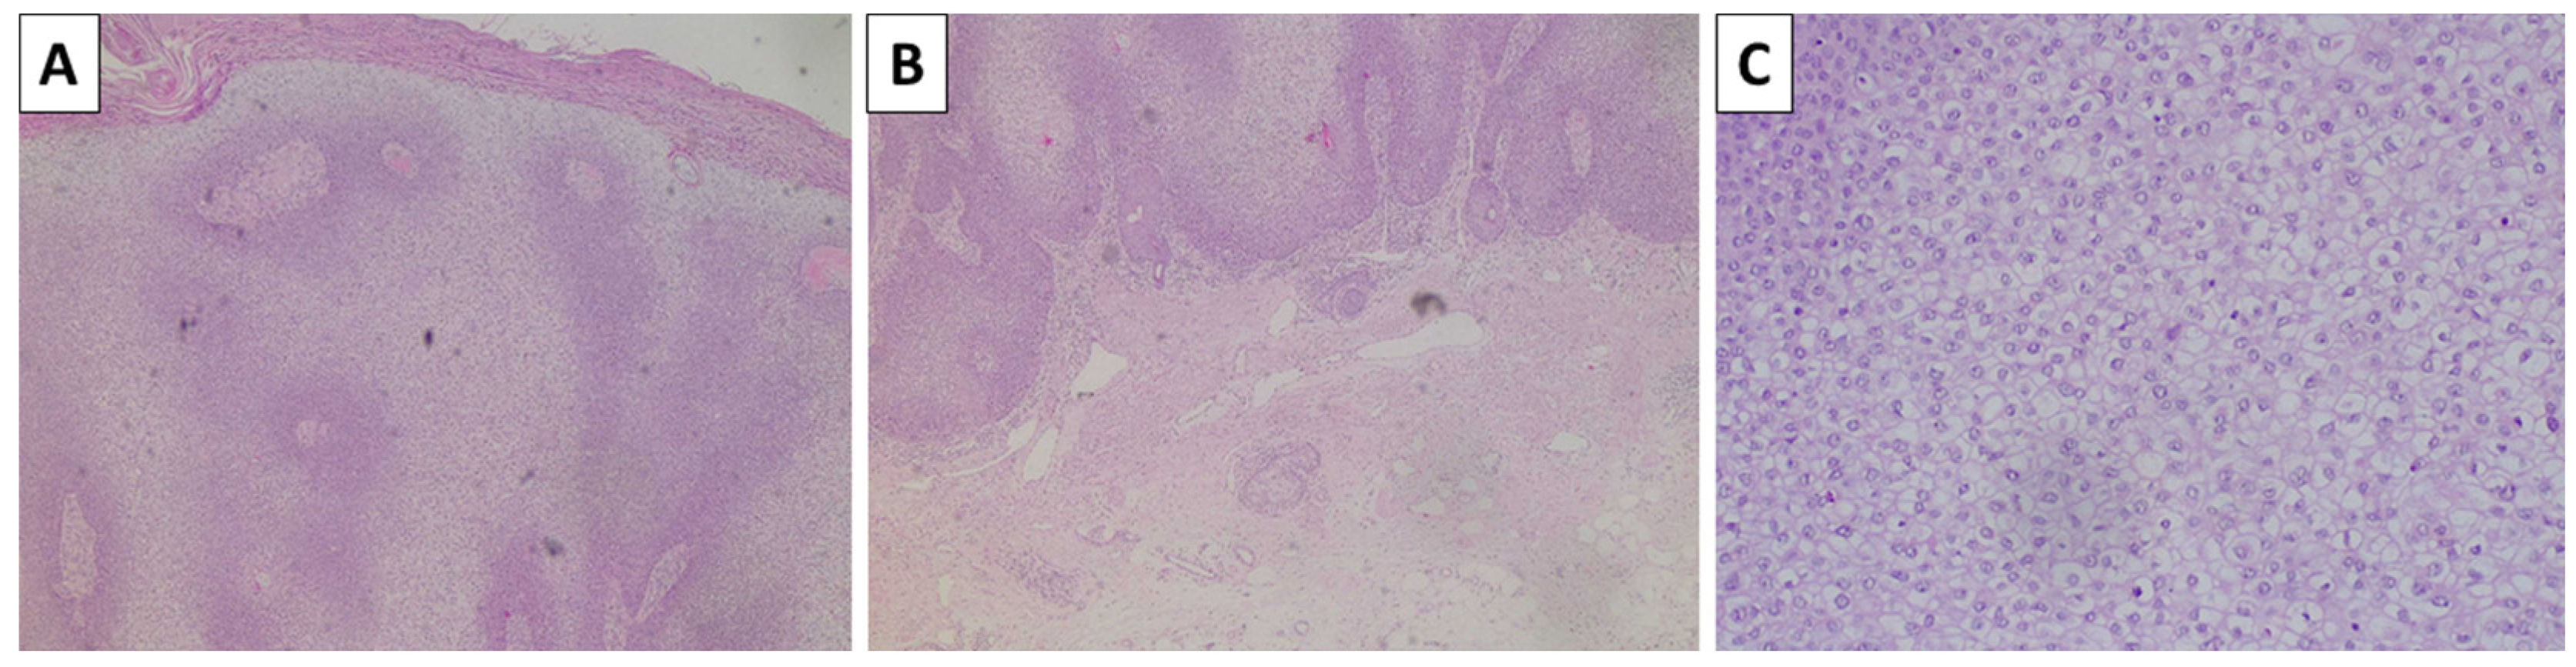

2.3. Case 4—Cellular Blue Nevus as a Secondary Finding in a Patient with In Situ Clear Cell Squamous Cell Carcinoma and Superficial Spreading Melanoma